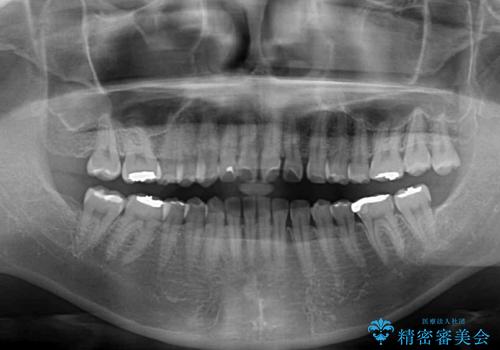

- 前歯の隙間を気にして来院された患者様です。

隙間、捻転ともに軽微でありましたが、下顎前歯の突き上げにより隙間ができていたため、インビザラインを用いて咬み合わせを改善しながら前歯の歯列を整えていくこととしました。

治療途中に上顎前歯は失活してしまいましたが、変色が顕著ではないため、経過を見ていくこととなりました。